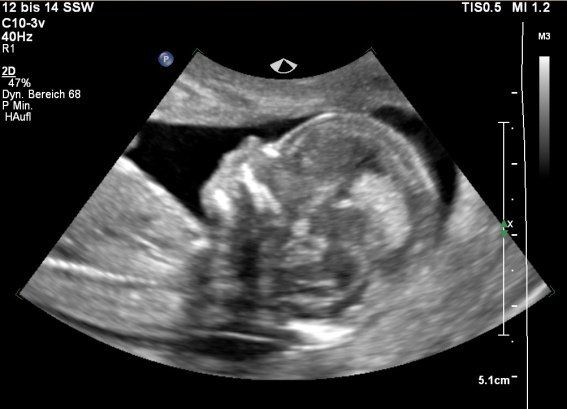

12. SSW: Embryo, SSL 51 mm

Button

Fet: 13. SSW

Fet: 14. SSW